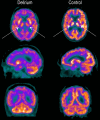

Methods: We assessed cerebral glucose metabolism using 18 F-fluorodeoxyglucose positron emission tomography (FDG-PET) in sick, older patients with and without delirium, all without clinical dementia (N = 20). Strict exclusion criteria were adopted to minimize the effect of established confounders on FDG-PET.

Results: Patients with delirium demonstrated hypometabolism in the bilateral thalami and right superior frontal, right posterior cingulate, right infero-lateral anterior temporal, and left superior parietal cortices. Regional hypometabolism correlated with delirium severity and performance on neuropsychological testing.

Discussion: In patients with acute illness but without clinical dementia, delirium is accompanied by regional cerebral hypometabolism. While some hypometabolic regions may represent preclinical Alzheimer's disease (AD), thalamic hypometabolism is atypical of AD and consistent with the clinical features that are unique to delirium.